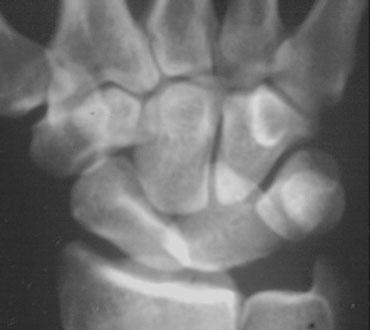

Phân tích:

1. Gãy xương thuyền và mỏm trâm trụ.

2. Cung I và II bị gián đoạn tại khớp LT (nguyệt-tháp).

3. Có sự song song giữa xương nguyệt và cực gần xương thuyền với xương quay.

4. Xương thuyền bị ngắn lại (foreshortened), cho thấy nó đang nghiêng và di chuyển về phía lòng bàn tay.

5. Tất cả các xương cổ tay còn lại đều có tính song song, ngoại trừ xương nguyệt, cực gần xương thuyền và xương quay.

Mặc dù đây có thể là trật khớp quanh nguyệt, nhưng chỉ dựa vào tư thế PA rất khó để phân biệt đây là trật khớp xương nguyệt hay trật khớp quanh nguyệt. Hình dạng tam giác của xương nguyệt có thể là kết quả của việc chỉ nghiêng đơn thuần hoặc trật khớp kèm nghiêng.